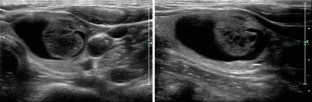

Fig. 1

Fig. 2